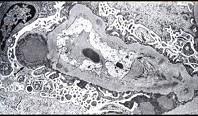

问题 阅读下面两张图片(电镜箭头示上皮下驼峰状电子致密物沉积)后,其病理诊断为 ( )

选项 A.急性间质性肾炎 B.系膜增生性肾小球肾炎 C.新月体性肾小球肾炎 D.膜增生性肾小球肾炎 E.毛细血管内增生性肾小球肾炎

答案 E